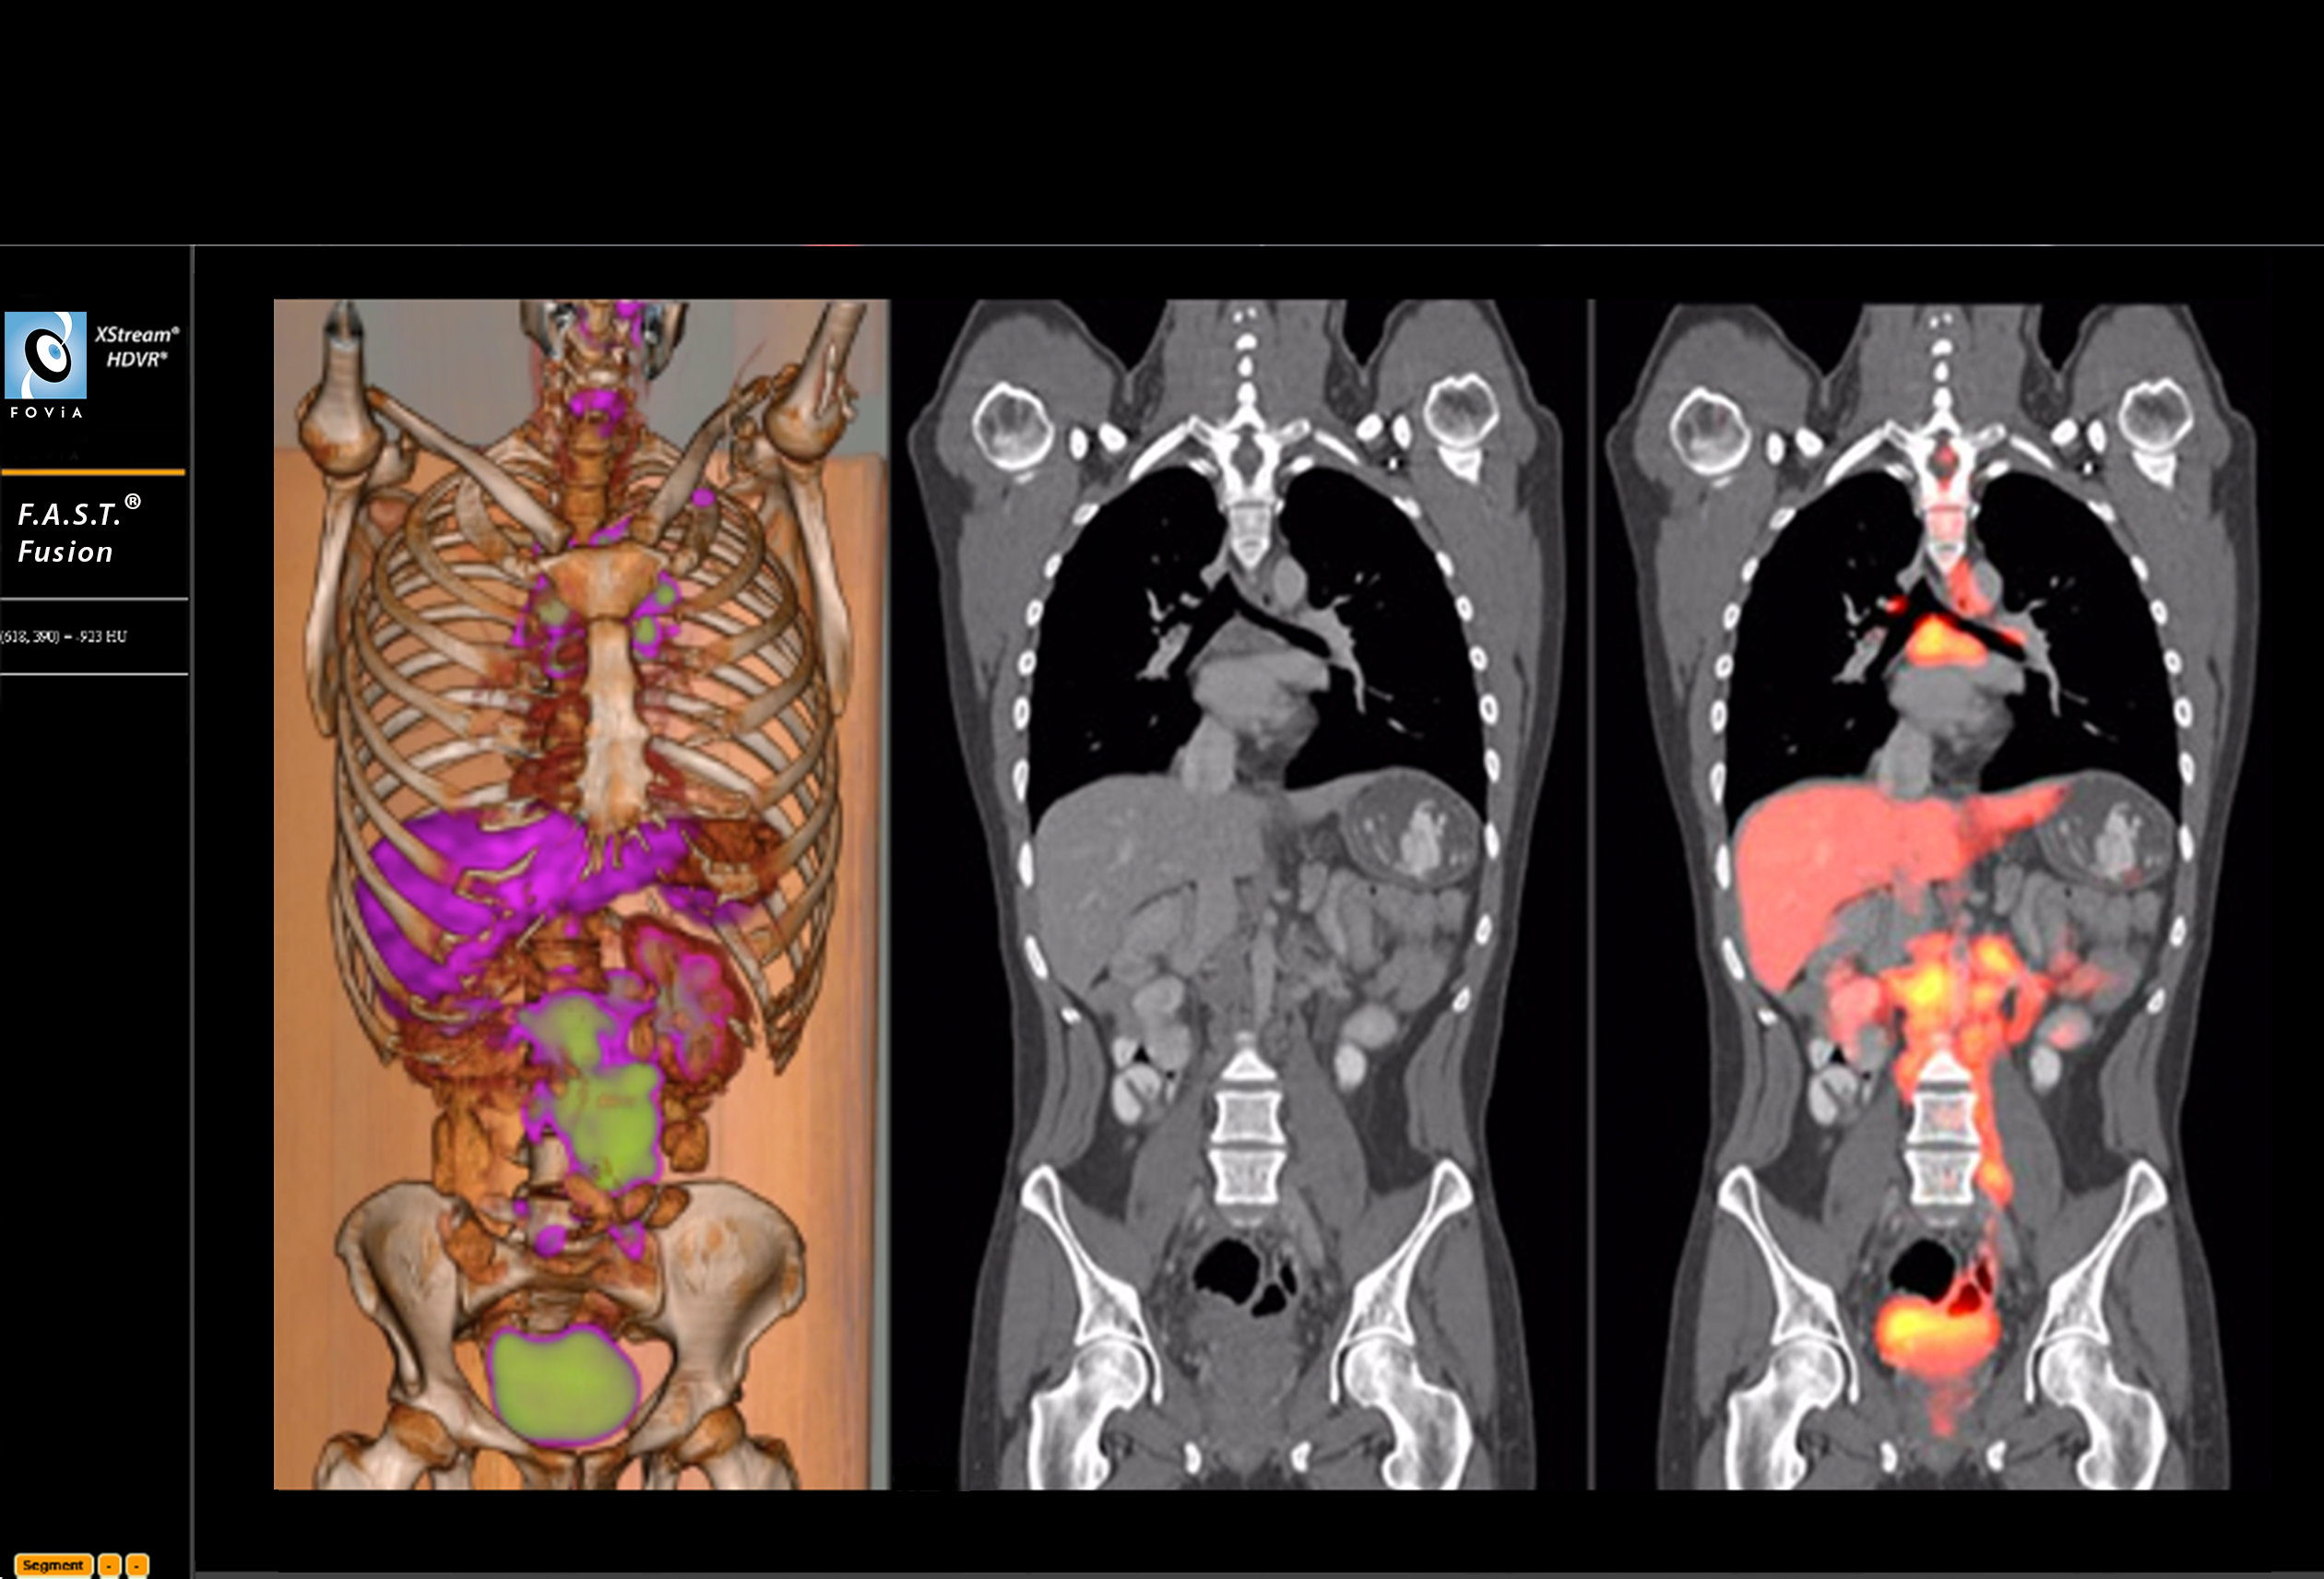

F.A.S.T. Fusion Workflow

F.A.S.T. Fusion Workflow